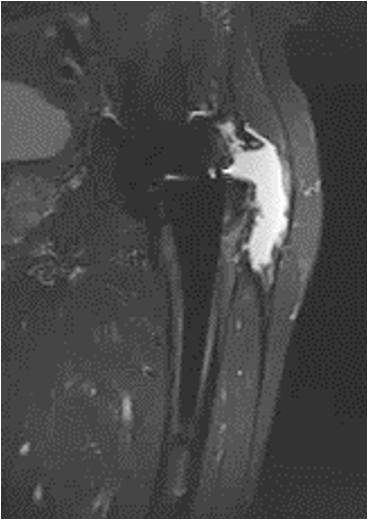

Adverse Local Tissue Reactions (ALTR)

Mechanism

Generation of biologically active, nanometer sized metal particles

- cause large inflammatory reaction

- pseudotumour (AKA aseptic lymphocyte-dominant vasculitis associated lesion ALVAL)

- can cause extensive soft tissue and bone loss

Diagnosis

Pain

High serum ion levels

Loosening on xray

Pseudotumour on MRI

Incidence

- 288 Depuy ASR THA 6 years post surgery

- moderate or severe ATLR in 24% on MRI